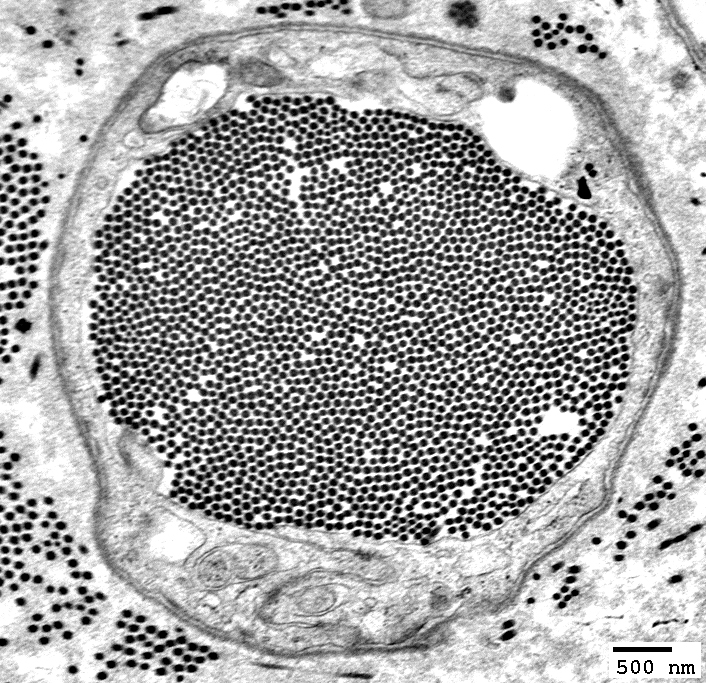

Myelin fragmentation in Post-myelinating (Autophagic) Schwann cells

Electron micrograph: From Robert E Schmidt MD

Myelin Degradation: Later phase

Autophagic Schwann Cells contain

Lipid debris

Myelin fragments, small

Axons: Lost